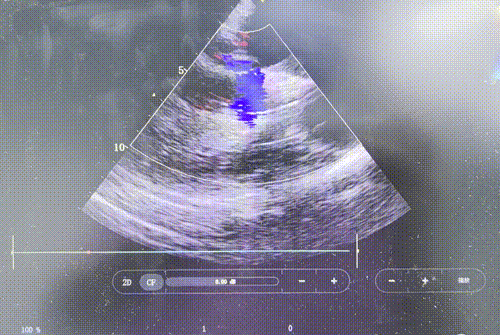

患者主动脉瓣重度反流纠正,术后无反流、无瓣周漏。术后心脏彩超显示人工生物瓣启闭良好,平均跨瓣压差3mmHg,流速正常。患者恢复情况良好,心功能较术前有了明显改善。

术前超声

术后超声长轴、短轴